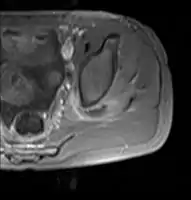

| Transverse T2 magnetic resonance imaging section through the hip region showing abscess collection in a patient with pyomyositis. | |